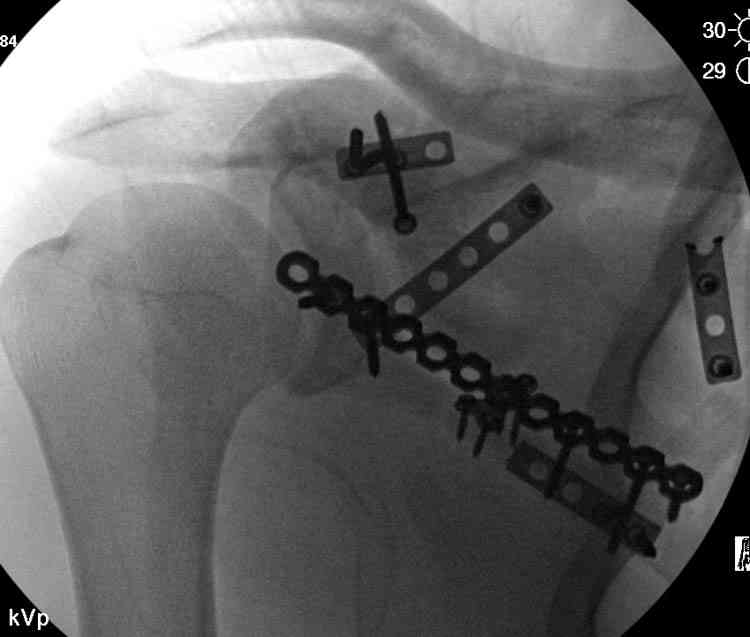

Двумя шурупами сзади на пластине (вместе шайбы)

провели удержание репозиции, а фиксацию провели

следующим косым шурупом.

Последующие этапы на снимках.